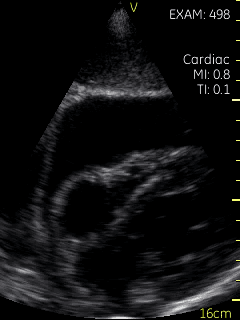

Video S3: Subcostal view of the heart taken after volume repletion in the dialysis unit. The right atrial collapse is no longer seen.

The case is of a 35-year-old male with acute pericarditis complicated by a large pericardial effusion with no evidence of tamponade clinically. The initial POCUS images show mild partial collapse of the right atrium with a small (< 2cm) and collapsing (> 50%) inferior vena cava (IVC) suggesting volume depletion.  The patient then received 500 cc of fluids during his scheduled dialysis session and a repeat POCUS scan 3 hours later shows near resolution of the right atrial collapse.

The physiologic findings of tamponade may occur earlier and at lower intra-pericardial pressures in hypovolemic patients. This phenomenon is known as “low pressure tamponade”. Clinical recognition of low pressure tamponade may be difficult because most patients lack the typical physical findings of pulsus paradoxus and distended neck veins. In the case of our patient, the small (< 2 cm) and collapsing (> 50%) inferior vena cava suggested a low right atrial pressure of approximately 3 mmHg.  Although a formal diagnosis requires a cardiac catheterization measuring intrapericardial and right atrial pressures, it is likely that our patient was in the very early stages of low-pressure tamponade that improved with the administration of fluids. Patients with low pressure tamponade may improve with fluids initially, but more severe cases often require aspiration of the effusion [5,6].